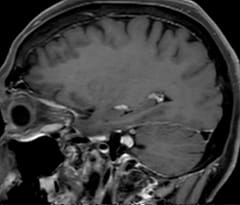

This is an example of acute ischemic stroke with distal occlusion of the right posterior cerebral artery. Note the improved visibility of the ischemic territory on the diffusion weighted image with high b-value. The 3D FLAIR shows a distal PCA occlusion. The fast SWIp depicts the thrombus on the isolated second echo image. The total scan time (including SmartBrain, preparations and a fast 3D T1w TSE Gd) is 8:00 minutes.

In this patient with acute right motor deficit and aphasia, the b2000 diffusion weighted image is normal. The SWIp image demonstrates more prominent veins in the right hemisphere, which could reflect increased deoxyhemoglobin contents. Fast ASL shows low CBF regions in the left frontal lobe. A follow-up ASL after one hour demonstrates high CBF values in the same area. The final diagnosis was migraine with aura.